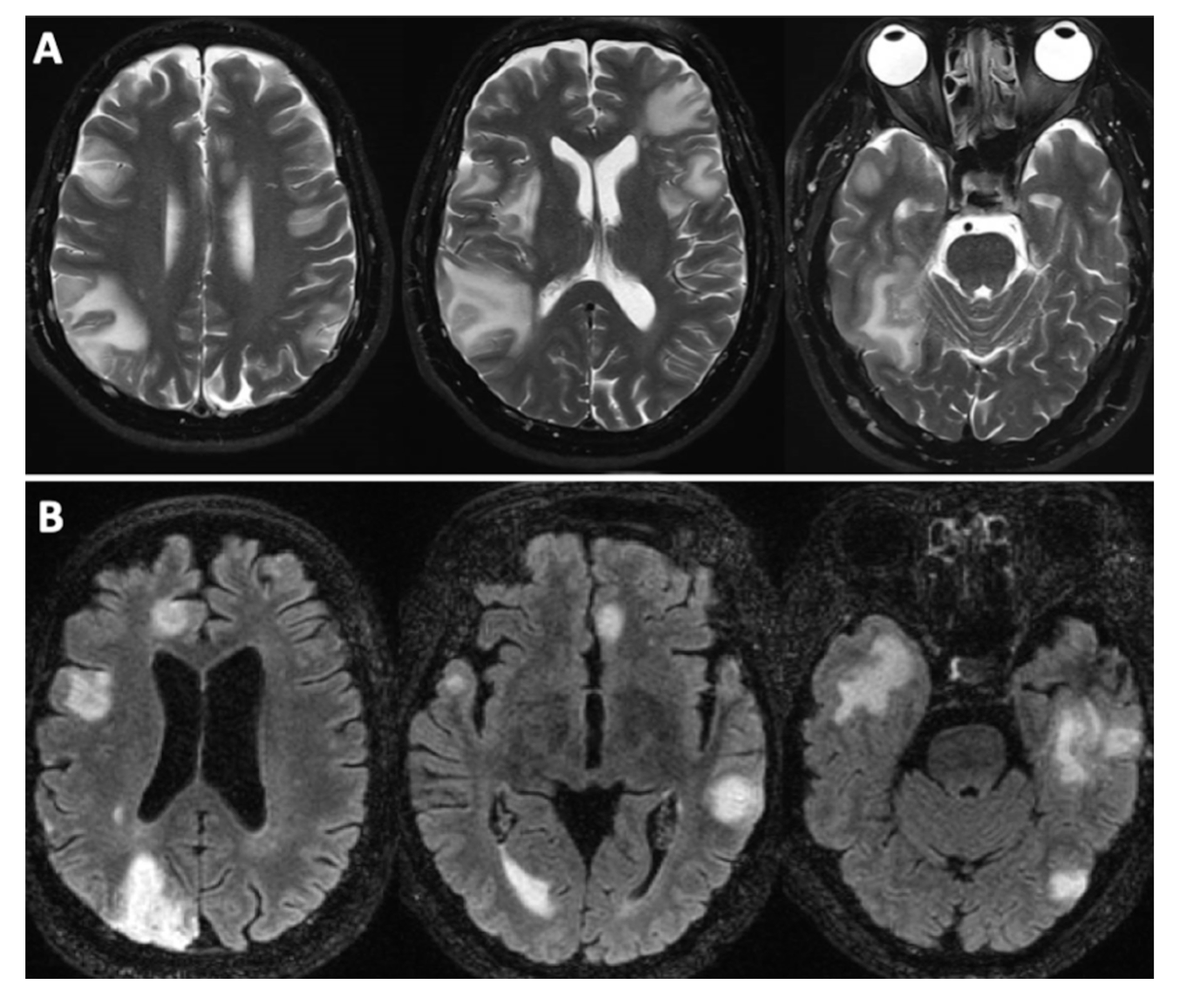

🧠Retired athletes with cognitive symptoms?

Take a careful head injury history, but don’t overcall CTE.